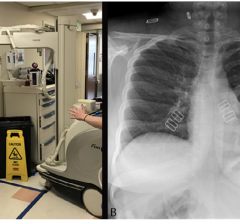

This page contains medical information for clinicians on the 2019 Novel Coronavirus (COVID-19, also called 2019-nCoV and now clinically SARS‐CoV‐2). This section includes articles on medical imaging of the virus for radiologists, new technologies being deployed to fight the virus and clinical information from various sources. Here are direct links for medical professionals to COVID-19 resources from the U.S. Food and Drug Administration (FDA), Centers for Disease Control (CDC) and the World Health Organization (WHO). Daily world-wide statistics on the coronavirus outbreak are available from the WHO Situations Reports. Centers for Medicare and Medicaid Services (CMS) frequently asked questions and answers (FAQs) for healthcare providers regarding Medicare payment for laboratory tests and other services related to the COVID-19

May 1, 2020 — The Radiological Society of North America (RSNA) COVID-19 Task Force has published a guidance document on ...

April 23, 2020 — A special report published in the journal Radiology outlines prevention, diagnosis and treatment of ...

April 23, 2020 — A new expert panel consensus statement published simultaneously in the journals Radiology: Imaging ...